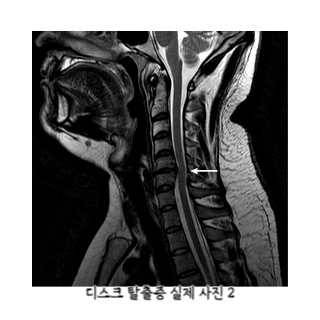

3.1 경추 디스크 탈출증

경추(목 부위 척추) 디스크의 탈출로 인해 주변 신경이 압박되면 어깨 통증이 발생할 수 있습니다. 이는 목과 어깨 사이의 방사통을 야기합니다.

경추 디스크 탈출증으로 인한 어깨 통증의 증상

- 목에서 어깨로 이어지는 방사통

- 어깨 및 팔의 저림 또는 감각 이상

- 목과 어깨 근육의 경직 및 압통